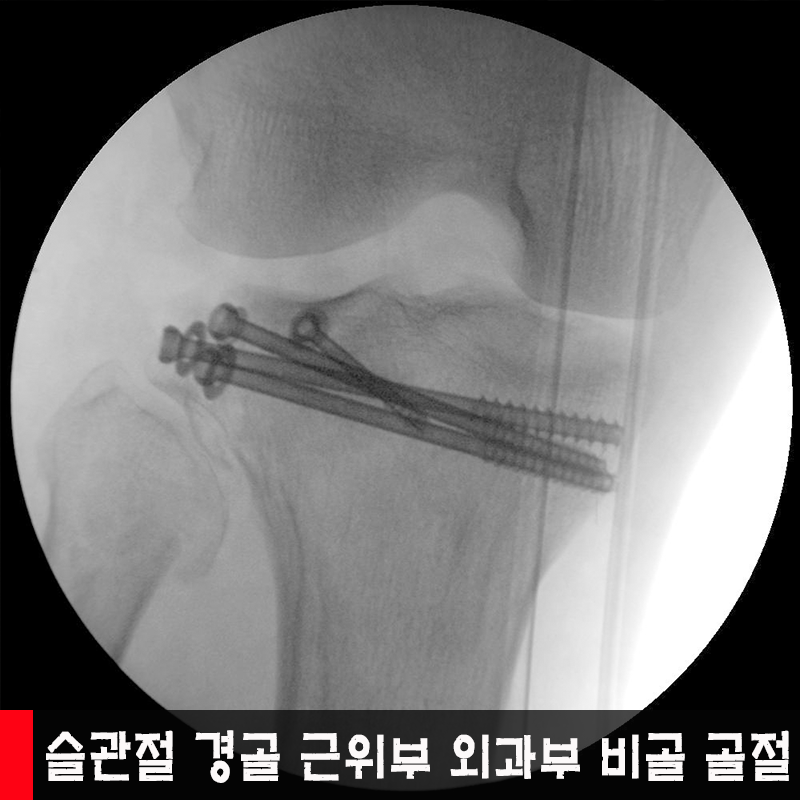

°ß°©°ñ °ñÀý, ¿ìÃø½½°üÀý °ß°ñ ±ÙÀ§

¿ÍºÎºÎ ¹× ºñ°ñ±ÙÀ§ °ñÀý, ½½°üÀý °ñÀý

¨è ¿ìÃø °ß°©°ñ üºÎ °ñÀý